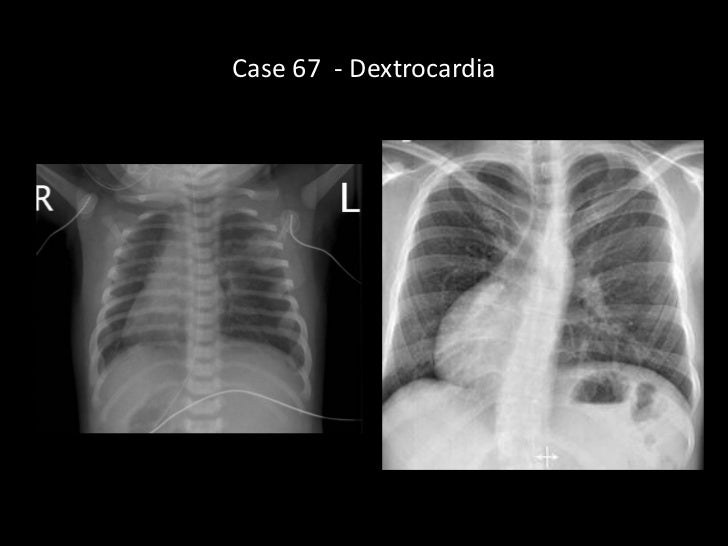

Dextrocardia case study picture This image representes dextrocardia case study.

This case is reported because of the situs inversus, dextrocardia and asplenia with early symptomatic presentation due to complex pattern of cardiac malformation. Checking the credentials of our writers can give you the peace of mind that you are entrusting your project to qualified people. Dextrocardia case study essay writing company. Dextrocardia case study, custom mba essay writer sites ca, sample resume format form, sociological concepts to write an essay about. Nice prices, excellence of writing and on-time delivery.